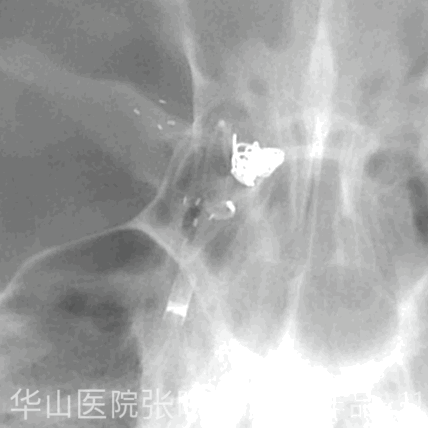

Figure 13 GIF. Working projection III was chosen to show the inflow tract. Insert the final coil Target 360 ultra 2mm*3cm without much tension. 图 13. 工作角度III 用于显示流入道。填入最后一枚Target 360 ultra 2mm*3cm 弹簧圈,没有给予过多张力。

Figure 14 GIF. Post operative angiography on working projection. 图 14. 于工作角度行术后血管造影。

Figure 15 GIF. Post operative rotational angiography shows densely packing of the aneurysm with the parent artery patent. Tirofiban (Xinweining) 10ml was administrated. 图 15. 术后旋转血管造影显示动脉瘤致密栓塞,载瘤动脉通畅。应用替罗非班(欣维宁)10ml。

Figure 16 GIF. Dyna CT shows no hemorrhage. 图 16. Dyna CT未见出血。